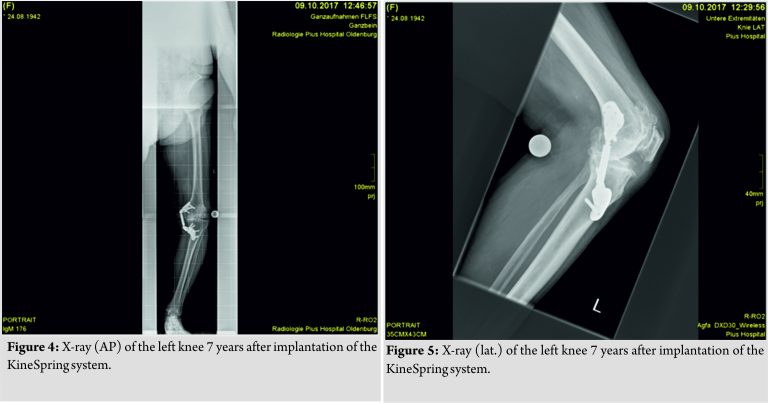

The KineSpring procedure followed standard techniques that have already been described [10]. The patient remained hospitalized for 3 days following the procedure. She reported immediate arthritic pain relief postoperatively. For more than 6 years, she remained pain free and the KineSpring joint unloading system functioned well. At the end of October 2017, the patient presented to clinic with increasing the left knee pain. She reported increasing pain with weight-bearing and knee flexion and had been taking anti-inflammatory medication as needed. The knee was stable in varus and valgus testing, although testing was ratherdifficult due to the KineSpring implant. Radiographically, there were signs of a severe osteoarthritis of the lateral and the patellofemoral compartment (Fig. 4 and 5).